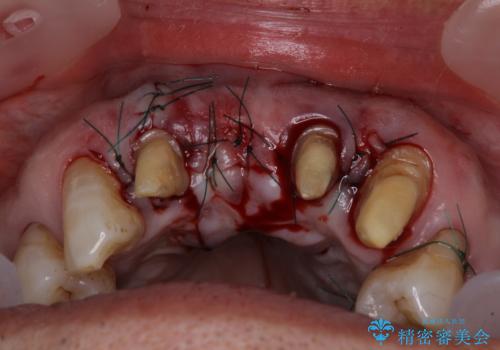

上顎の奥歯は全体的に歯周ポケットが散見され出血が認められたため、歯周外科処置を行うこととしました。

上の歯は見た目を良くしたいというご希望があったため、歯周外科処置を行った歯についてはセラミッククラウンで補綴することとしました。

また、前歯の部分矯正も希望されたため、歯周外科処置と平行して矯正治療を行うこととしました。

- 外科手術のため、術後に痛みや腫れ、違和感を伴います

- 歯周組織再生治療は患者様の状態によって術後の経過が異なります(見た目が改善しない場合もあります)